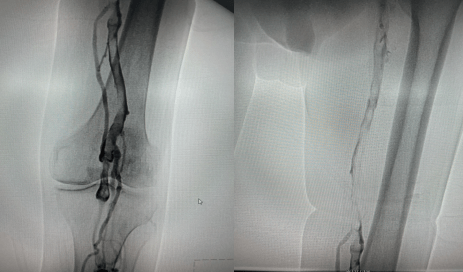

留置接觸性溶栓導管并微量泵人尿激酶溶栓(50萬U/日),小劑量溶栓既降低溶栓出血風險、又保證了療效;溶栓72小時后,拔除溶栓導管,復查造影左下肢深靜脈血流通暢,血栓全部消失,達到預期效果。

復查造影左下肢深靜脈血流通暢,血栓完全消失